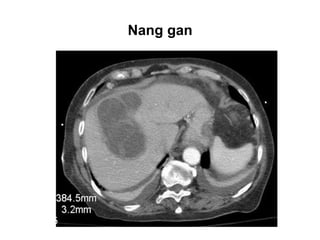

Nang gan

- Cấu trúc dịch: dịch trong các nang thận, dịch thấm có tỉ trọng gần với

tỉ trọng nước. phụ thuộc nhiều vào lượng protein có trong dịch. Dịch

nang là dịch vô mạch, nên tỉ trọng sẽ không đổi khi tiêm thuốc cản

quang tĩnh mạch.